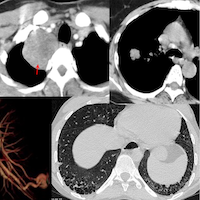

65-yrs old with PH and RV dysfunction for evaluation. Initially considered for edge-to-edge tricuspid repair.

CMR showed a cause of the PH, which could potentially change management.